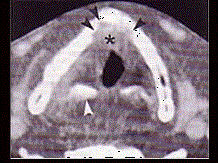

问题 男,60岁,因吞咽疼痛伴咽异物感一个月就诊。间接喉镜下检查发现会厌侧面轻度糜烂、不光滑、隆起,既往有吸烟史。 CT检查见下图,进一步的检查是 ( )

选项 A、放疗 B、活检送病理 C、密切观察 D、抗生素治疗 E、纤维喉镜检查以明确病变范围

答案 B

解析 B